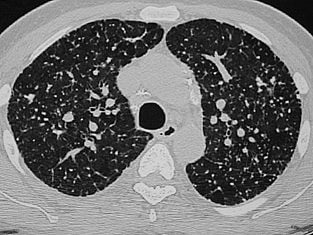

सांगली ः कोरोना रुग्णांची एचआरसीटी करणे काही प्रकरणात आवश्‍यक ठरत असून त्यात खुलेआम लूट सुरु झाली आहे. कुणीही कितीही दर आकारत आहे. या प्रकरणी राज्य शासनाकडे मोठ्या प्रमाणात तक्रारी दाखल झाल्या होत्या. त्यानंतर आता दिलासादायक बातमी असून राज्य शासनाने एचआरसीटी अर्थात सिटीस्कॅन करण्याचे दर निश्‍चित करण्यासाठी समिती गठीत केली आहे. पुढील सात दिवसांत पूर्ण अभ्यास करून सिटीस्कॅनचे कमाल दर ठरवण्याचे आदेश दिले आहेत.

याआधी रुग्णालये आणि खासगी प्रयोगशाळांमध्ये आरटीपीसीआर, रॅपीड अँटीजेन आणि रॅपीड अँटीबॉडी तपासण्यांसाठी दर निश्‍चित केले आहेत. आता एचआरसीटी करण्यासाठीचे दरही निश्‍चित होती. राज्य आरोग्य हमी सोसायटीचे मुख्य कार्यकारी अधिकारी सुधाकर शिंदे यांच्या अध्यक्षतेखाली सायन हॉस्पिटलच्या रेडीऑलॉजी विभागप्रमुख अनघा जोशी, जेजे रुग्णालयाचे अधिष्ठाता आणि आरोग्य सेवा आयुक्तालयाचे संचालक अशा चार जणांची समिती असणार आहे. रुग्णालये आणि एचआरसीटी केंद्रांशी चर्चा करून हे दर निश्‍चित केले जाणार आहे. तसे आदेश राज्य शासनाचे प्रधान सचिव डॉ. प्रदीप व्यास यांनी दिले आहेत.